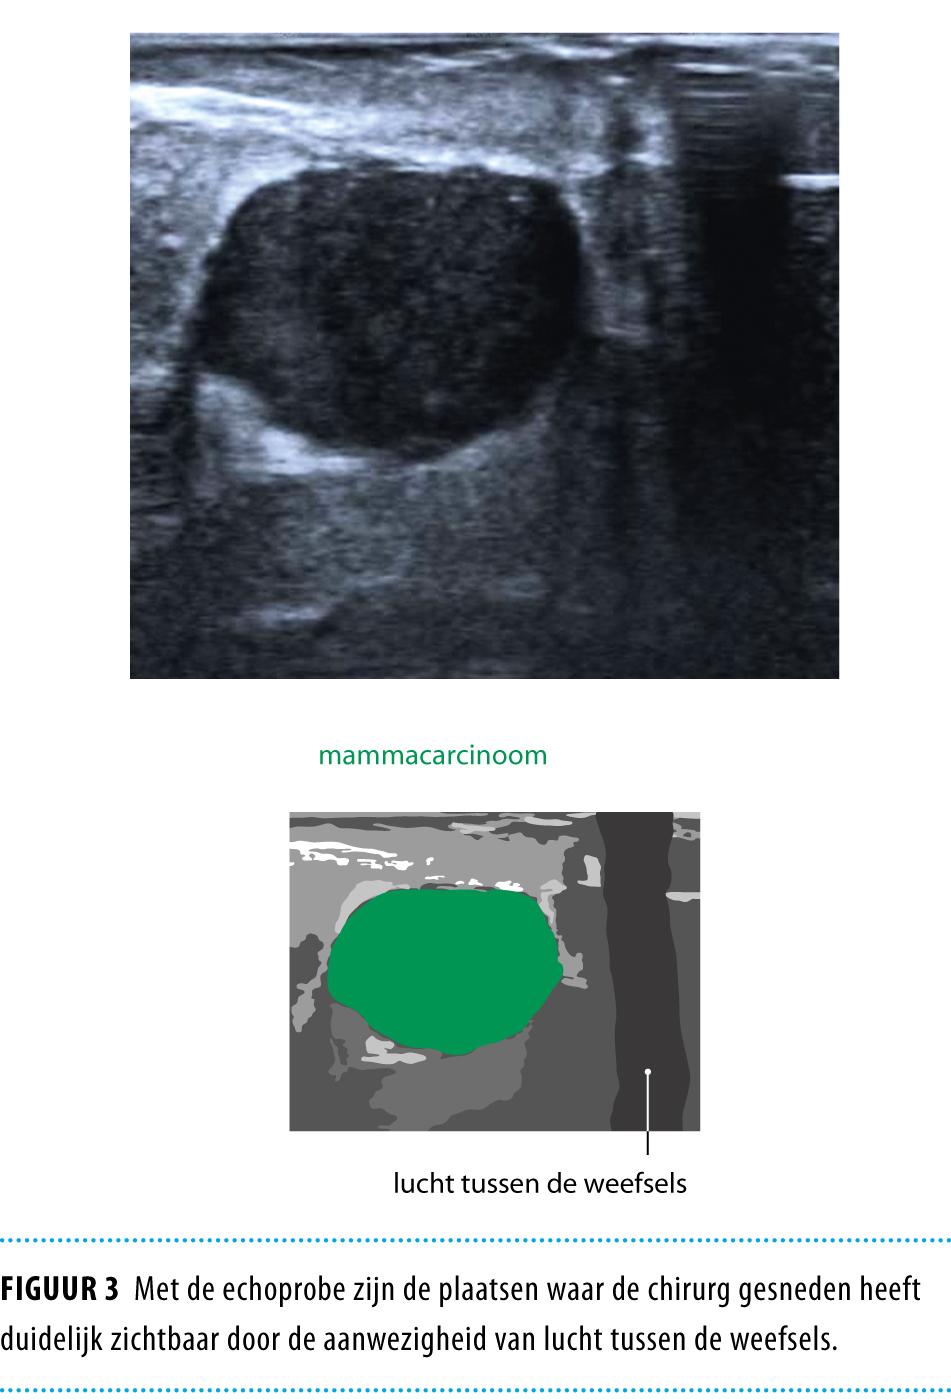

De hoeveelheid weefsel die geëxcideerd zal worden, wordt bepaald met de huidmarkeringen en echografie. Tijdens de operatie wordt de echoprobe vanuit verschillende richtingen in en rond de wond geplaatst, zodat de locatie en diepte van de tumor continu bekend zijn (figuur 2). Met de echoprobe zijn de plaatsen waar de chirurg gesneden heeft duidelijk zichtbaar door de aanwezigheid van lucht tussen de weefsels (figuur 3). Zo kan gecontroleerd worden of een adequate marge rondom de tumor is behouden zonder dat te veel gezond mammaweefsel wordt verwijderd.

Figuur 3